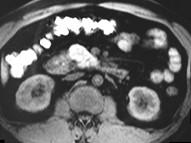

问题 男,43岁,上腹胀痛2个月,频繁呕吐,呕吐物为黄绿色,影像所见如图,可能的诊断为()

选项 A.十二指肠溃疡 B.十二指肠结核 C.十二指肠中分化腺癌 D.十二指肠克罗恩病 E.十二指肠淋巴瘤

答案 C